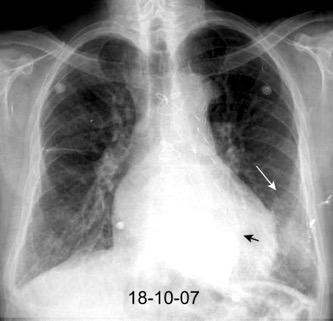

Rotura esofágica

Laceración transmural espontánea.

Excesos en comida y/o bebida

Marzo 2014: Perforación longitudinal distal secundaria a episodio de vómito (síndrome de Boerhaave). Derrame pleural izdo. que evoluciona a empiema.

Wang C-T et al. Tension hydropneumothorax in a Boerhaave syndrome patient: A case report . World J Emerg Med, 2021. Katabathina V et al. Nonvascular, nontraumatic mediastinal emergencies in adults:a comprehensive review of imaging findings. Radiographics. 2011.